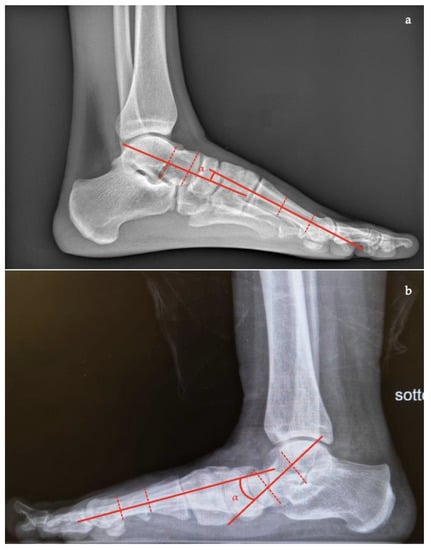

- Talar–first metatarsal angle (Meary’s angle), the normal value is 0 ± 10 degrees and is increased in flatfoot deformity (often >20°, apex directed plantarly) (Figure 5);

- Calcaneal pitch, the angle between the line parallel to the ground and the line along the inferior inclination axis of the calcaneus (normal, 20–30°; flatfoot, <20°) (Figure 6);

- Talocalcaneal angle is formed by the long axis of the rearfoot and the midtalar line. This angle is increased in pronated feet on both the AP and lateral views (normal <45°, flatfoot >45°) (Figure 7);

- Calcaneal-fifth metatarsal angle, defined as the angle formed between the tangent to the inferior aspect of the calcaneus and a line drawn along the inferior aspect of the base and head of the fifth metatarsal (normal <170°, flatfoot >170°) (Figure 8).